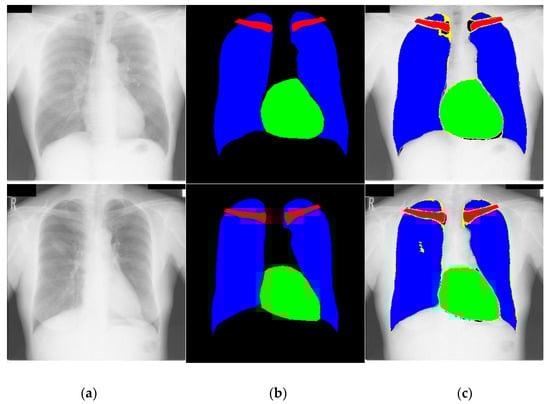

4.3.1. Chest Anatomy Segmentation Testing Using CardioNet

4.3.5. Automated Computation of CTR by the Proposed Method